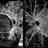

- OCT Angiography, proliferative diabetic retinopathy (PDR), Diabetes, CIRRUS 5000 ANGIOPLEX, NVE

Zeiss Cirrus 5000 - Description

- OCT-Angiography 8x8 Montage OU. PDR with active NVE OD. 37 year old male with no visual complaints. Vision is 20/20 in both eyes.